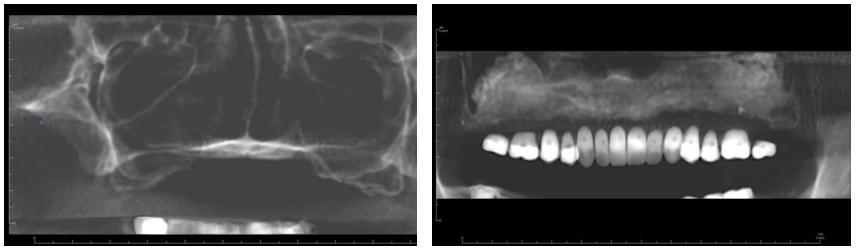

Figure 1. 62-year-old female with Class V ridge. Redundant flabby tissue on the ridge with little bone support and inability to wear a full denture. Patient underwent bilateral sinus lifts, vertical and horizontal ridge augmentation with a tissue engineering triad technique with PRP as the stem cell source. This patient was treated in the office.

Figure 2 (a & b). Pre op panorex (left) showing highly pneumatized sinus short anterior ridge height anterior. Post op (right) panorex with imaging guide, bilateral sinus lifts and vertical and horizontal ridge augmentation.

Figure 3 (a & b). Pre and post-operative sagittal cone beam views of ridge augmentation revealing excellent horizontal and vertical gains.